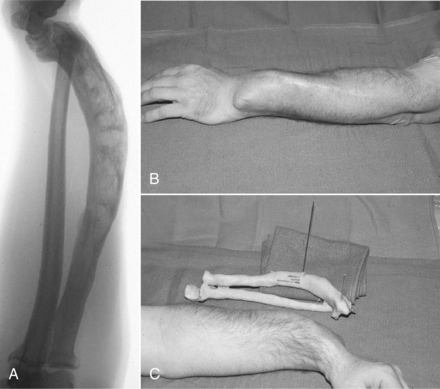

Musculoskeletal.: The progressive deossification that weakens the bony structure primarily affects the axial skeleton. The lesions occur at multiple sites, particularly the skull, spine, pelvis, femurs, and tibias. Pathologic fractures can occur in any bone (Fig. 24-9), especially in the proximal femurs, pelvis, and lumbar spine.

Figure 24-9 Paget’s disease. A complex malunion of the radius in a 62-year-old man after several fractures. A, The presenting lateral radiograph of the severe deformity. B, The clinical appearance. C, A bone model made from computed tomographic scans and used for preoperative planning for correction of the deformity. (From Browner BD: Skeletal trauma: basic science, management, and reconstruction, ed 3, Philadelphia, 2003, WB Saunders.)